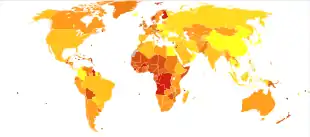

Down syndrome is the most common chromosomal abnormality in humans.[9] Globally, as of 2010, Down syndrome occurs in about 1 per 1,000 births[1] and results in about 17,000 deaths.[133] More children are born with Down syndrome in countries where abortion is not allowed and in countries where pregnancy more commonly occurs at a later age.[1] About 1.4 per 1,000 live births in the United States[134] and 1.1 per 1,000 live births in Norway are affected.[9] In the 1950s, in the United States, it occurred in 2 per 1,000 live births with the decrease since then due to prenatal screening and abortions.[93] The number of pregnancies with Down syndrome is more than two times greater with many spontaneously aborting.[10] It is the cause of 8% of all congenital disorders.[1]

Maternal age affects the chances of having a pregnancy with Down syndrome.[4] At age 20, the chance is 1 in 1,441; at age 30, it is 1 in 959; at age 40, it is 1 in 84; and at age 50 it is 1 in 44.[4] Although the probability increases with maternal age, 70% of children with Down syndrome are born to women 35 years of age and younger, because younger people have more children.[4] The father's older age is also a risk factor in women older than 35, but not in women younger than 35, and may partly explain the increase in risk as women age.[135]